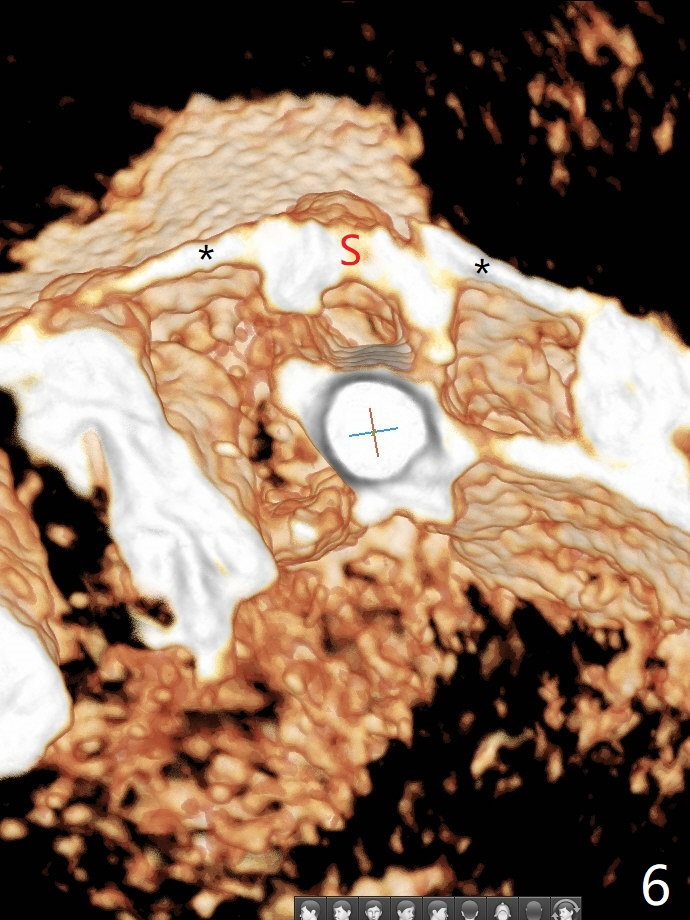

防止拔牙后颊侧骨板萎缩最有效方法是保留部分牙根,例如颊侧(外形象盾牌,简称盾,socket shield (S)),但是制备特别麻烦,尤其是上尖牙。60岁女右上3颊侧骨板隆起(图一至三:*),但是相当狭窄(上下方向),预计强行拔除,势必损失颊侧骨板,造成颊侧塌陷,准备保留盾,如图三红虚线,图六(术后3D长轴断面(十字架:植体))S代表。其实术中试图将整个牙根一起拔除,但是仿佛不行,只好静下心来分根,制备盾,不过困难重重,尤其是除去根尖(防止残余感染),最长外科裂钻似乎达不到根尖,取出后者,颊侧根尖骨板穿孔(图七:箭头)。然后腭侧钻洞(图四),当最后一个钻头保持原位时,在颊侧根尖穿孔处植入粘性骨粉(从牙槽窝口进入,原本粘性骨粉为了修复大面积颊侧缺损用(万一需要强行拔除)),然后才把一段式植体植入(图五),在其余空间填入骨粉,稍微制备基台,制作临时牙冠,最后在牙槽窝开口塞入PRF膜,衬里牙冠,不暂时取出牙冠,衬里相当于临时粘固剂。术后一个月牙根片段和临时牙冠维持良好的牙龈外形(图八,九);术后两个月病人嫌尖牙龈端太尖太长,临时牙冠龈端调整(图十,十一),但愿一个月后龈缘合乎病人期望。